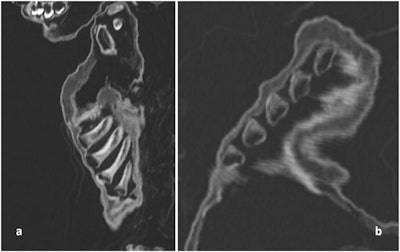

Nerlich's group used CT to conduct a virtual autopsy, measuring the boy's bone lengths and assessing his lungs. The team also performed radiocarbon testing.

The child's soft tissue showed that he was overweight for his age. But his ribs had a malformation pattern called rachitic rosary, which is often caused by rickets or scurvy.

CT also showed pleural adhesions in the baby's right lung, suggesting that he had pneumonia -- an illness to which children suffering from rickets are more vulnerable -- and which may have contributed to his death, the team noted.